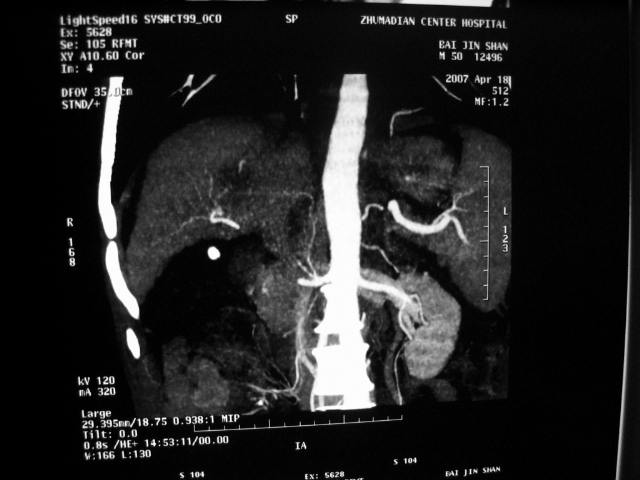

标题: CT7751:病人,50岁,肝硬化多年,行CT三期扫描 [打印本页]

标题: CT7751:病人,50岁,肝硬化多年,行CT三期扫描

肝硬化 脾大 胃底静脉曲张 肝癌 门腔间淋巴结肿大

肝癌、肝硬化、脾大、门静脉高压、胃底静脉曲张.

肝硬化、脾大,静脉曲张,肝右叶低密度灶,增强无明显强化,还是考虑肝癌可能性大,建议结合afp检查。

考虑肝硬化,脾大,静脉曲张,肝右叶低密度灶,右肝癌可能性大。

肝癌分为肝细胞性和胆管细胞性,从强化表现来看,确切地说应是胆管细胞癌.